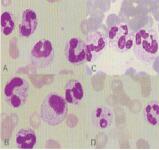

1、異型淋巴細(xì)胞:在病毒(如腺病毒、人類皰疹病毒等)、原蟲(如弓形蟲)感染,藥物反應(yīng),結(jié)締組織疾病,免疫系統(tǒng)強(qiáng)應(yīng)激狀態(tài)或過敏原等因素刺激下,淋巴細(xì)胞增生并發(fā)生形態(tài)上的變化,表現(xiàn)為胞體增大、胞質(zhì)量增多、嗜堿性增強(qiáng)、細(xì)胞核母細(xì)胞化,稱異型淋巴細(xì)胞或反應(yīng)性淋巴細(xì)胞。外周血異型淋巴細(xì)胞主要是T細(xì)胞(83%~96%),少數(shù)為B細(xì)胞(4%~7%)。異型淋巴細(xì)胞按形態(tài)特征分為3型:Ⅰ型(空泡型)又稱泡沫型或漿細(xì)胞型(傳統(tǒng)認(rèn)為最常見),Ⅱ型(不規(guī)則型)又稱單核細(xì)胞型(現(xiàn)認(rèn)為最常見),Ⅲ型(幼稚型)又稱未成熟細(xì)胞型或幼淋巴細(xì)胞型。

異型淋巴細(xì)胞的形態(tài)特點(diǎn)